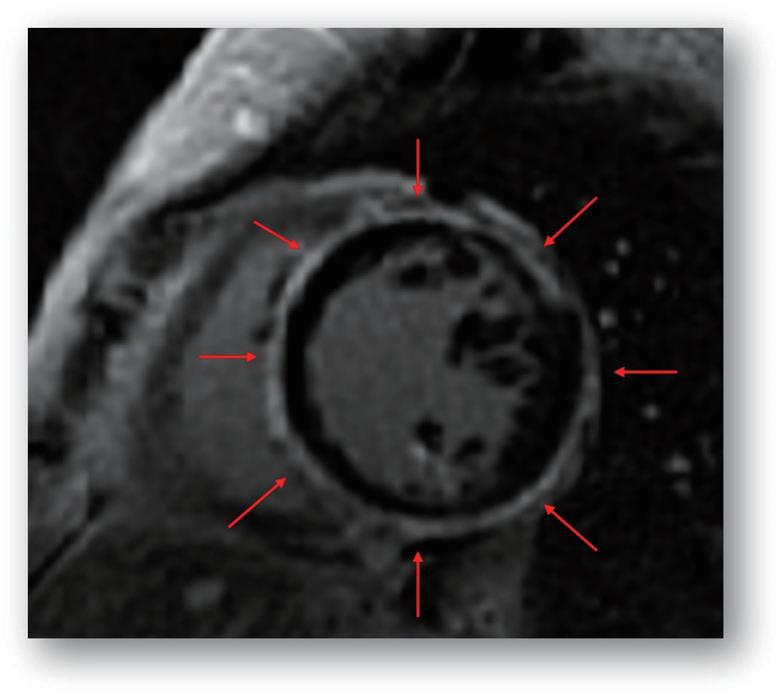

5. 環狀分佈模式

在特定病例中,心室瘢痕呈現環狀分佈模式 (Ring-like Pattern) ,這種模式涵蓋三個或以上的心室短軸段,見 於家族性或復發性心肌炎患者。此模式會涉及多處心室壁,但並不顯著影響左心室的收縮功能,具有高風險 的心律不整。 (圖三)